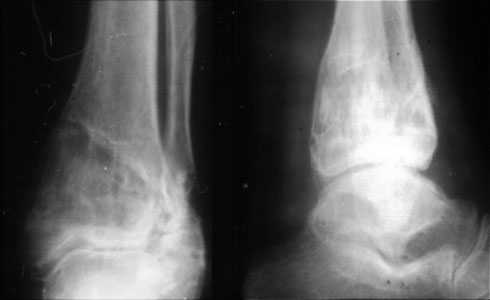

Аппаратом можно сделать все минимально инвазивно и травматично, вырастить клиновидный регенерат после чрескожной остеотомии через один или два разреза 0,5 см. В приложении похожий по локализации случай, только более давние последствия травмы с замыканием части зоны роста, деформация побольше, плюс укорочение голени было.

Уважаемый Александр то что вы показали это интересно, но это два разных случая. В ваших снимках большая деформация, которая требует выращивания массивного регенерата, поэтому здесь согласен лучше аппарат, а представленном случае дефект будет небольшой поэтому накостный синтез решит все проблемы за 2 недели без ключей 8*10 в течении 3-5 месяцев.Зачем себе создавать головную боль.